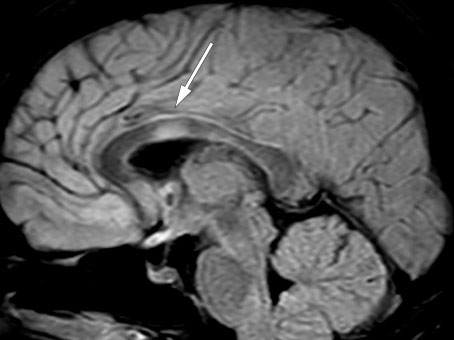

To måneder etter utskrivelsen fra nevrologisk avdeling ble vakthavende lege kontaktet av rehabiliteringssenteret fordi pasienten opplevde gradvis økende hodepine og kvalme samt redusert syn på venstre øye siste døgn. Vakthavende øyelege fant visus 0,05 på venstre øye og 1,2 på høyre, og mistenkte optikusnevritt. Vakthavende nevrolog fant uvuladeviasjon mot venstre og bilateralt inverterte plantarreflekser. Lumbalpunksjon viste moderat økt celletall, totalprotein og IgG (tabell 1). MR caput viste økt signal i thalamus bilateralt uten andre forandringer i hjernen og økt signal i nervus opticus bilateralt og i chiasma opticum (figur 3). Pasienten fikk igjen metylprednisolon, som hadde rask effekt.

Myelitt og bilateral optikusnevritt er hovedkjennetegn for nevromyelitis optica-spektrum-sykdommer. Selv om pasienten ikke tidligere hadde hatt antistoffer mot akvaporin-4 eller MOG, fremsto dette nå som sannsynlig diagnose, og antistoffprøver fra serum og cerebrospinalvæske ble tatt på nytt. Man valgte å utføre PET-CT og mammografi, da nevromyelitis optica-spektrum-sykdommer hos eldre kan være relatert til brystkreft.